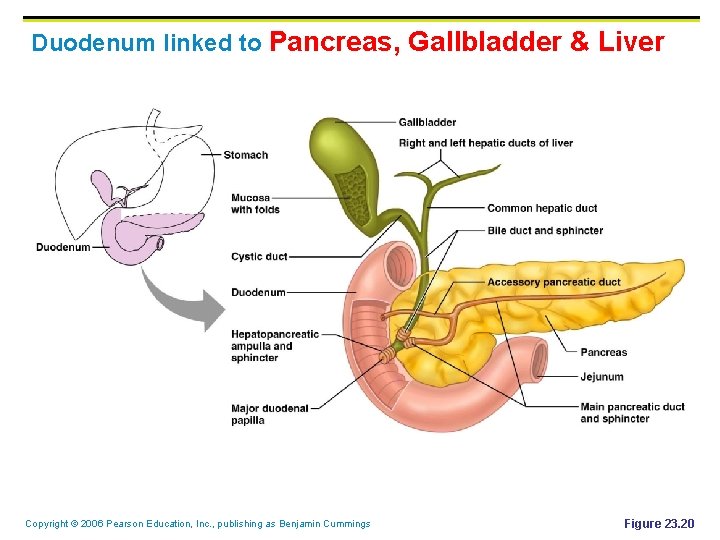

Duodenum linked to Pancreas, Gallbladder & Liver Copyright © 2006 Pearson Education, Inc. , publishing as Benjamin Cummings Figure 23. 20

Liver (largest organ in body) & Gallbladder § Bile is produced in the liver and the Gallbladder stores bile Copyright © 2006 Pearson Education, Inc. , publishing as Benjamin Cummings

Gallbladder and Associated Ducts Copyright © 2006 Pearson Education, Inc. , publishing as Benjamin Cummings Figure 23. 20

Composition of Bile § § A yellow-green, alkaline solution containing bile salts, bile pigments, cholesterol, neutral fats, phospholipids, and electrolytes Bile salts are cholesterol derivatives that: § Emulsify fat § Facilitate fat and cholesterol absorption § Help solubilize cholesterol Copyright © 2006 Pearson Education, Inc. , publishing as Benjamin Cummings

Pancreas § Location § § Lies deep to the greater curvature of the stomach The head is encircled by the duodenum and the tail abuts the spleen Copyright © 2006 Pearson Education, Inc. , publishing as Benjamin Cummings

Pancreas § Exocrine function § § Secretes pancreatic juice which breaks down all categories of foodstuff The pancreas also has an endocrine function – release of insulin and glucagon (hormones) Copyright © 2006 Pearson Education, Inc. , publishing as Benjamin Cummings